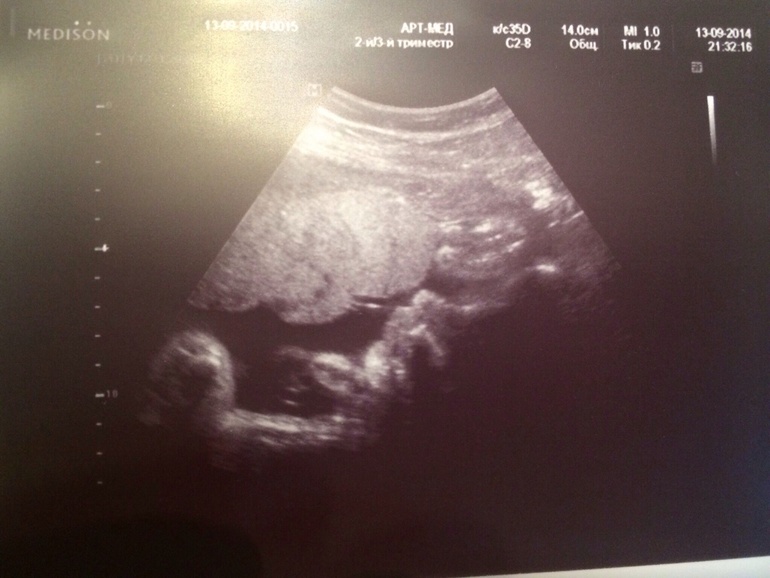

Вчера были на УЗИ!!!

Наш любимый мальчик так вырос!!)))

Лежал зевал, открывал ротик и как всегда закрывался ручками!!

Губы большие такие, как у мужа, волосики отросли длинные!!!)))

Весим 1884 г., все у нас хорошо, плацента только ей не очень понравилась!

Одно обвитие, говорят все свободно вокруг шеи и малышу это не мешает!

Лежим головой вниз, как я и думала, что сынуля бил меня ножкой вверх!!))